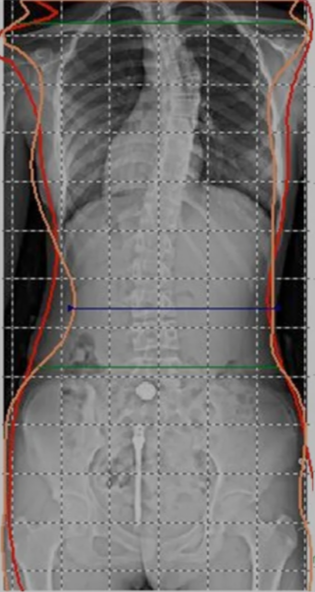

經(jīng)商國家衛(wèi)生健康委現(xiàn)答復(fù)如下: 脊柱側(cè)彎屬于脊柱彎曲異常的一種,是危害兒童青少年健康的常見疾病之一。嚴重者會損 傷脊髓和神經(jīng)根,甚至造成癱瘓、心肺功能障礙和其他器官系統(tǒng)疾病。兒童青少年脊柱彎 曲異常直接影響學(xué)習(xí)、生活和就業(yè),影響到國家人才培養(yǎng)的質(zhì)量。

將脊柱彎曲異常納入學(xué)生常見病監(jiān)測網(wǎng)絡(luò),早發(fā)現(xiàn),早治療 近期,國家正在制定新的學(xué)生常見病監(jiān)測計劃,擬將脊柱彎曲異常列為定期體檢項目,及 時發(fā)現(xiàn)脊柱彎曲異常,及早采取措施控制其發(fā)展,加強健康教育,提高兒童和家長對脊柱 彎曲異常的社會知曉率。教育系統(tǒng)在推進 “中小學(xué)健康促進行動” 中,積極倡導(dǎo)學(xué)生形成 良好健康行為,培養(yǎng)正確坐、立、睡、行姿勢習(xí)慣,保證足夠體育鍛煉和體力活動,保障 學(xué)生體育鍛煉時間,鼓勵學(xué)校采購符合標準的可調(diào)節(jié)課桌椅和坐姿矯正器。